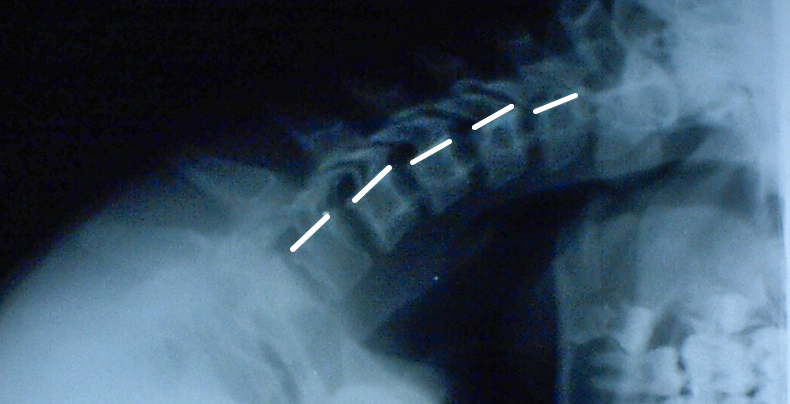

На фото: рентгенограмма шейного отдела позвоночника с наклоном вперед у ребенка 15 лет, небольшие «ступеньки» между телами позвонков – это норма.

Рентгенограмма шейного отдела позвоночника с наклоном вперед у ребенка 15 лет, небольшие «ступеньки» между телами позвонков – это норма.